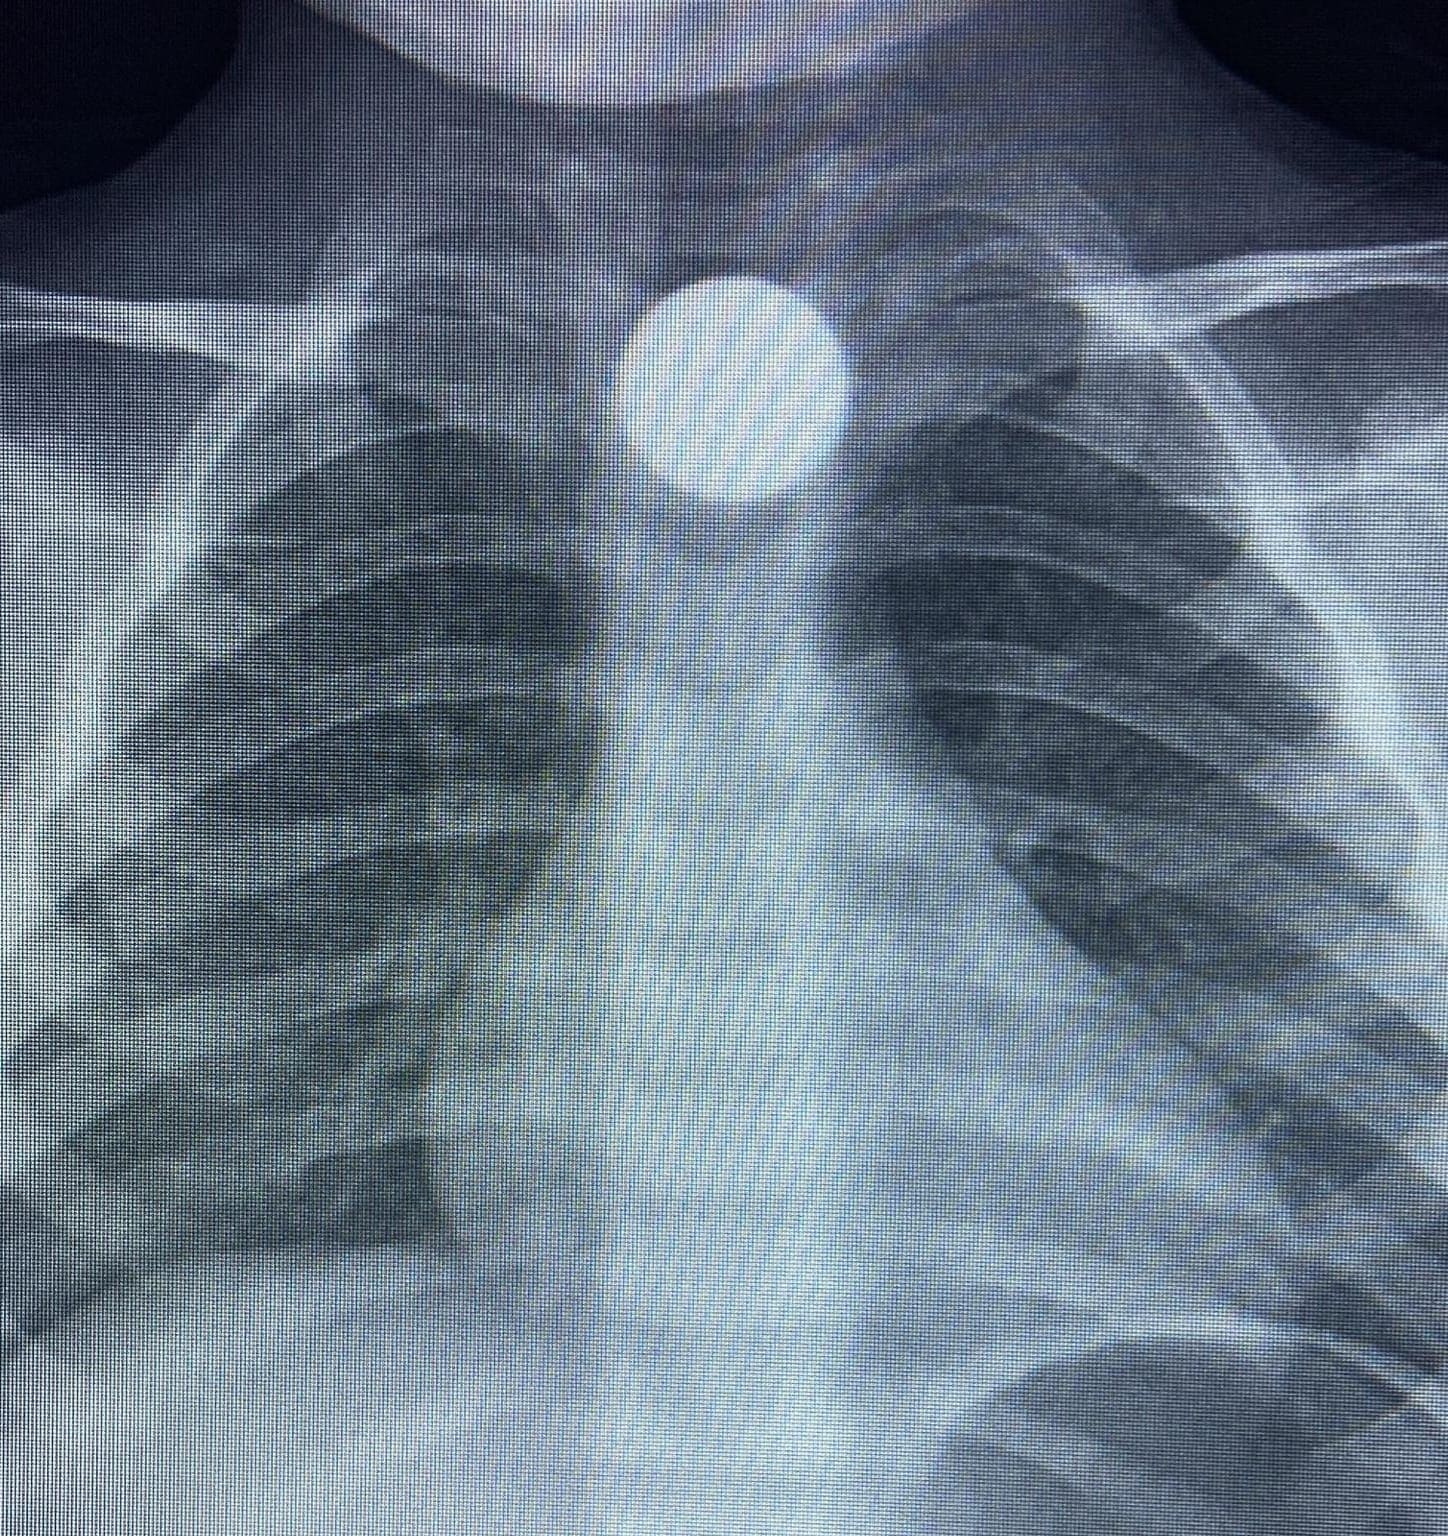

Hastanede yapılan radyolojik tetkikler sonucunda, 50 kuruşun mideye inmediği ve yemek borusunda takılı kaldığı tespit edildi. Hayati tehlike oluşmaması adına ilk müdahalesi İnegöl’de gerçekleştirilen Bilal K., daha donanımlı bir tedavi için ambulansla Bursa Yüksek İhtisas Eğitim ve Araştırma Hastanesi’ne sevk edildi.